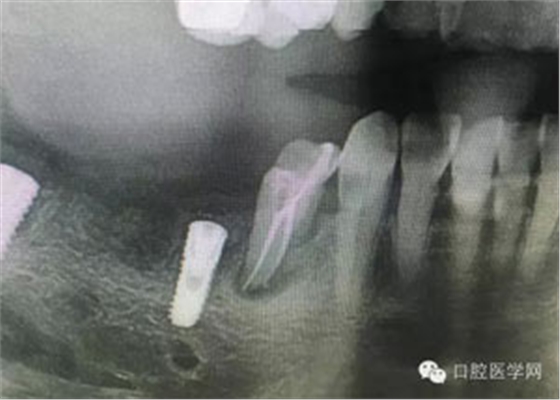

病例1:患者迫切希望保留自己的這一顆牙齒,根尖周陰影比較大,二度松動(dòng).而且旁邊有種植修復(fù)體,和患者溝通好后,治療好后觀察一個(gè)月后冠修復(fù),因?yàn)橛蟹N植的后期修復(fù),所以有了機(jī)會(huì)觀察,術(shù)后三個(gè)月和術(shù)后四個(gè)月,根尖恢復(fù)的還算不錯(cuò),希望能夠繼續(xù)觀察下去.這樣子的病例,做的時(shí)候我們一定要非常的小心,和患者要有充分的溝通以及不同科室的溝通然后決定怎么樣做比較好,假如就是出現(xiàn)了問(wèn)題,到時(shí)候我們也比較好處理些,免得我們自己到時(shí)候不好收?qǐng)觥?/span> 病例2:364647中齲的樹(shù)脂充填,現(xiàn)在樹(shù)脂的充填材料非常之多,有些時(shí)候,我們感覺(jué)有了好的材料我們就可以做出好的修復(fù),可是這是在我們有扎實(shí)的基本功的基礎(chǔ)上的,我們可以沒(méi)有那么好的樹(shù)脂,那么多的顏色選擇,修復(fù)的那么的逼真,但是我們至少要恢復(fù)患者牙齒的功能,將腐質(zhì)去除干凈,薄壁弱尖消除掉,選擇好適應(yīng)癥,給患者以盡可能好的修復(fù)。 來(lái)源于KQ88